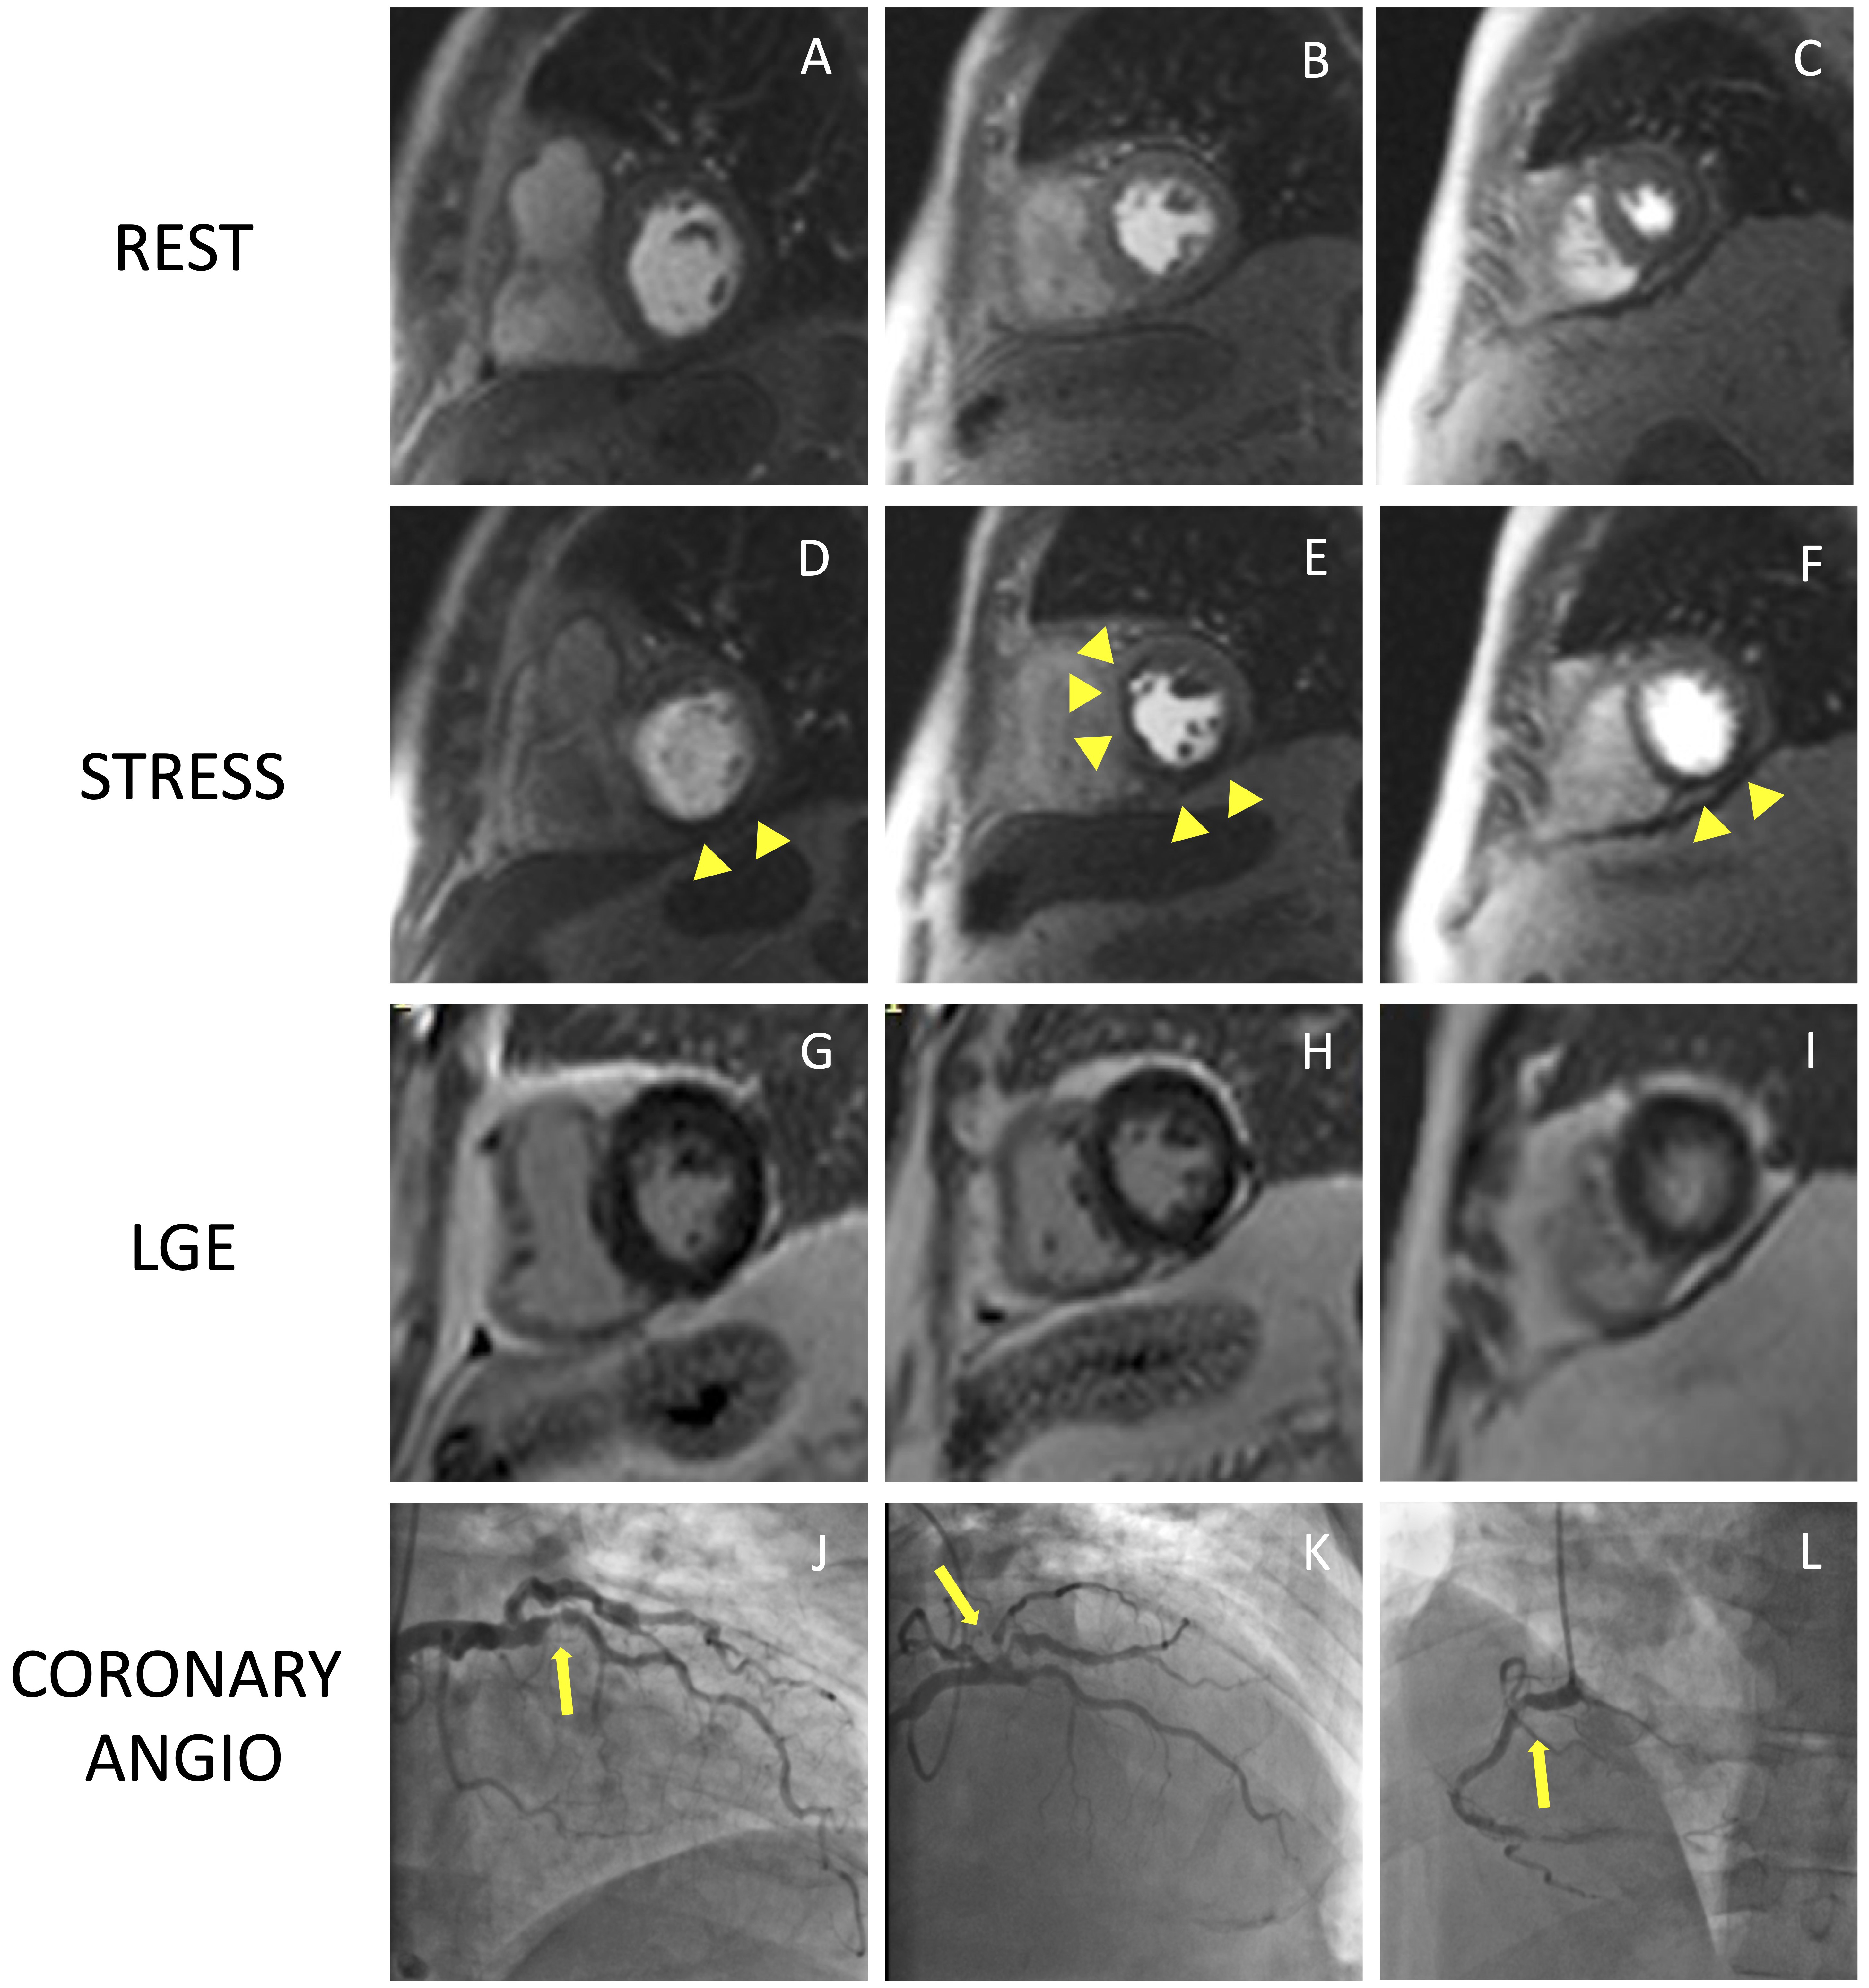

Stress CMR has been shown to be a safe and feasible technique, with good diagnostic quality. In a multicentre prospective registry of about 12,000 referral patients, stress CMR showed an excellent safety profile with higher incidence of mild complications and minor symptoms in dobutamine stress CMR compared to other vasodilators [33]. The safety of stress CMR has been demonstrated in patients with heart failure with reduced ejection fraction without any adverse event in a population of 1053 patients [34]. Stress CMR was well tolerated also in consecutive patients with MR-conditional pacemakers, with no significant change in lead thresholds or pacing parameters [35]. Pezel et al. [36] demonstrated the feasibility of vasodilator stress CMR in more than 600 patients with atrial fibrillation and suspected or stable coronary artery disease (CAD). Fig. 4 and Fig. 5 show two examples of stress CMR clinical cases. Fig. 6 shows how to implement stress CMR in clinical practice.

Fig. 4.

Fig. 4.Example of positive CMR adenosine-stress perfusion. We present the case of a 73-year-old man with new onset of ventricular arrythmia on exercise test and a history of previous ACS and RCA angioplasty. Short axis rest and stress perfusion images are shown respectively at the basal (A,D), mid-ventricular (B,E), and apical (C,F) level. The stress images show the presence of a perfusion defect, appearing as subendocardial hypointense area in the inferior septum, inferior wall and in the mid portion of the anterior and antero-septal walls (yellow arrow heads). Corresponding LGE images (G,H,I) show no myocardial scarring. The patient underwent a coronary angiography which revealed diffuse CAD with severe stenosis at the proximal tract of the LAD artery (yellow arrow line, J). and at the origin of the intermediate and the first diagonal branches (yellow arrow line, K). Moreover, there was an intrastent occlusion in the RCA with a collateral circulation (yellow arrow line, L). CMR, cardiovascular magnetic resonance; ACS, acute coronary syndrome; CAD, coronary artery disease; LAD, left anterior descending; LGE, late gadolinium enhancement; RCA, right coronary artery.